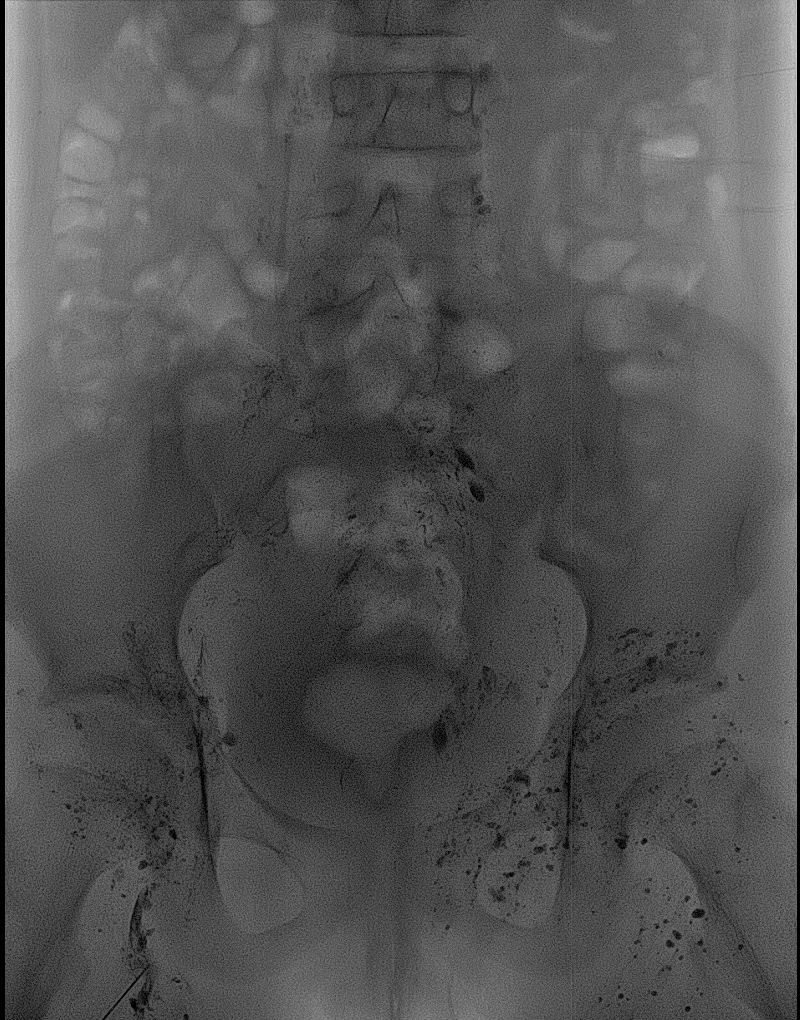

春节临近,四川大学华西第二医院放射科刘灵军博士带领介入医技护团队,成功为一例阴道乳糜瘘的13岁女性患儿以介入方式进行了“淋巴造影+硬化治疗手术”。在超声科万晋州老师的超声精准定位引导下,刘灵军博士用穿刺针进入直径不到1cm的淋巴结,然后在DSA监视下顺利实施淋巴结内造影及硬化治疗,同时经贵要静脉行胸导管逆行造影和疏通术。经过近7小时的奋战,手术非常成功。

该患儿患阴道乳糜瘘10多年,能明显感觉到会阴部不自主漏液,每日漏夜可完全浸湿6-8片尿不湿,生活质量差,严重影响患儿的身心健康。患儿父母带着患儿四处求医,辗转多家医院治疗无果后找到我院放射科介入亚专业组长刘灵军博士。刘灵军博士在充分了解患儿病情后,积极主动与临床多学科讨论,结合影像学检查诊断为“腹盆腔淋巴管发育畸形,与生殖系统有交通的异常发育的淋巴管破裂导致阴道乳糜瘘”,有介入手术指征。此类病例文献报道罕见,缺少成熟完整的手术方案。介入诊疗团队通过研究决定,在超声引导下穿刺腹股沟淋巴结行“淋巴造影和硬化治疗”,同时经贵要静脉行“胸导管逆行造影和疏通术”。医技护团队通力合作,连续奋战7个小时,以辛勤的汗水与精湛的技术相结合,顺利完成预定诊疗进程,术中患儿就自觉阴道漏液感消失,术后恢复良好。